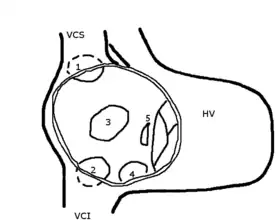

Le défaut de fermeture peut être situé :

- à la partie antérieure du septum interauriculaire, voire s'étendre sur le septum interventriculaire (canal atrio-ventriculaire). Elle prend alors le nom de communication de type ostium primum (5) et correspond à environ 15 % des cas découverts chez l'adulte[1] ;

- au milieu du septum interauriculaire, au niveau du foramen ovale. Ce sont les CIA de type ostium secondum, de loin les plus fréquentes (75 % chez l'adulte) (3);

- à la partie haute de la cloison, à proximité de l'abouchement de la veine cave supérieure; communication de type sinus venosus qui est toujours associé à un retour veineux pulmonaire droit anormal (1) : 10 % chez l'adulte.

- à la partie basse de la cloison, à proximité de la veine cave inférieure et du sinus coronaire (proche du retour veineux des vaisseaux du cœur ou coronaires) (4).